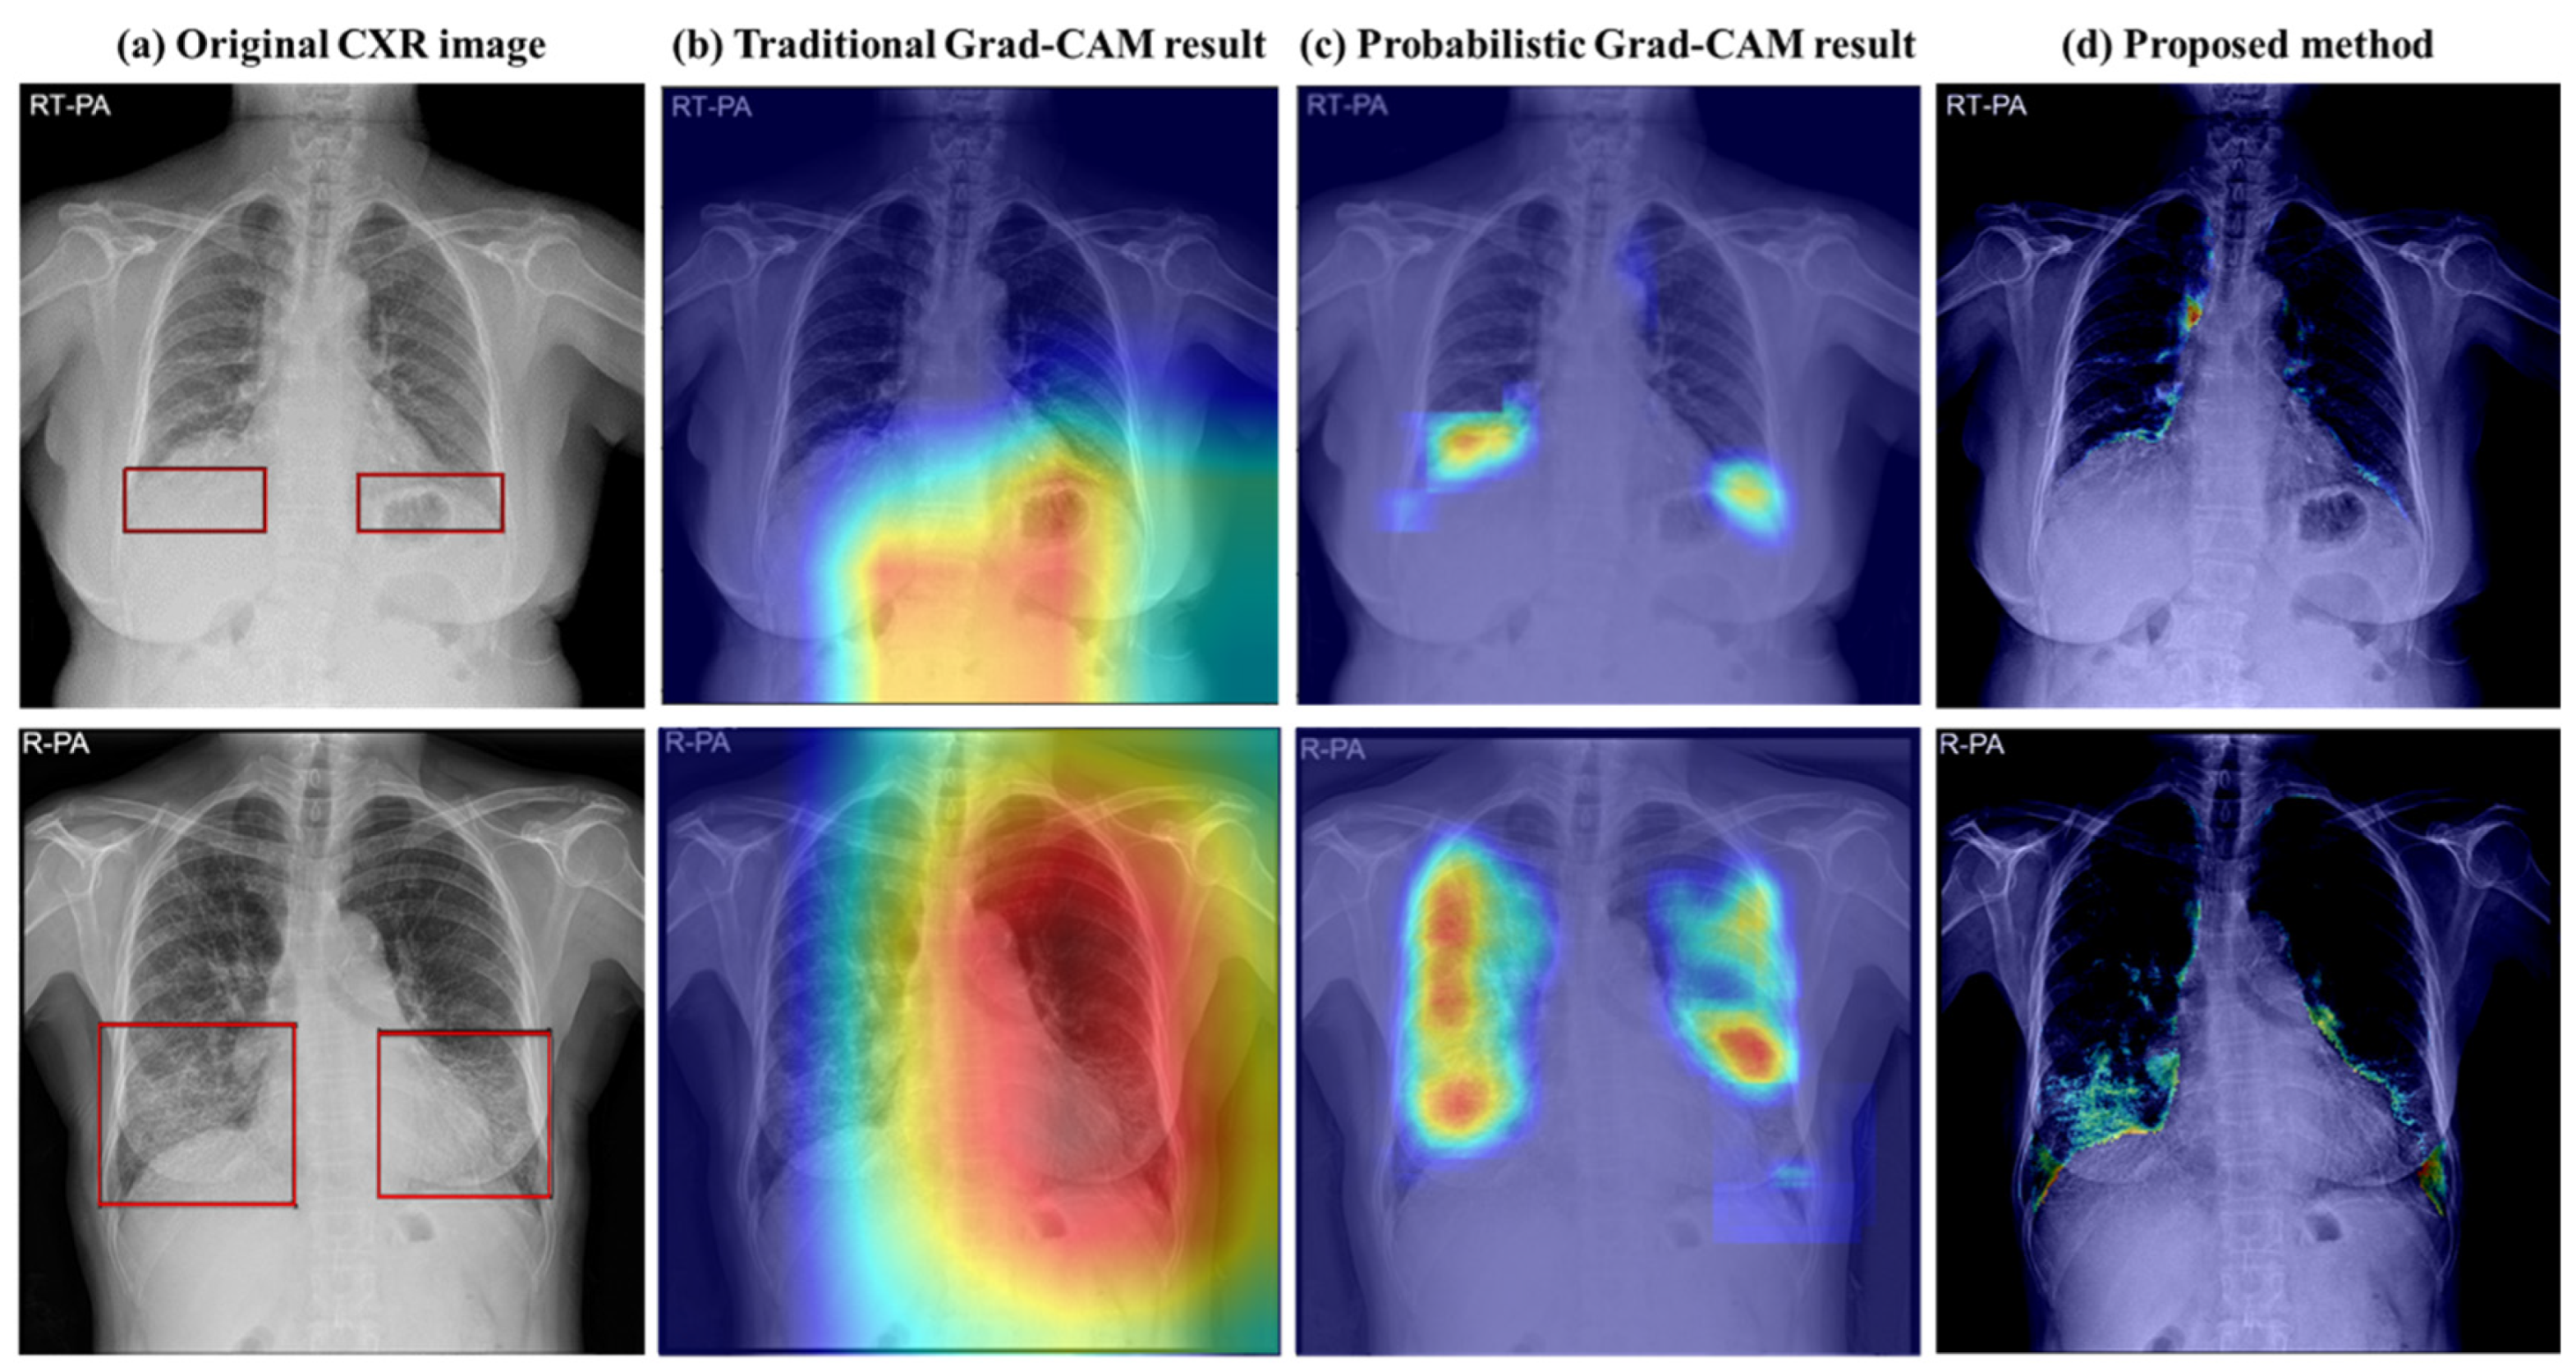

| Abnormal area detection | Probabilistic Grad-CAM [16] | 84.76% | 85.65% | 83.40% | 84.02% |

| Image-to-Image translation model | CycleGAN [18] with extent scoring algorithm | 81.20% | 73.14% | 89.16% | 76.96% |

| CUT [21] with extent scoring algorithm | 92.98% | 98.54% | 85.13% | 95.68% |